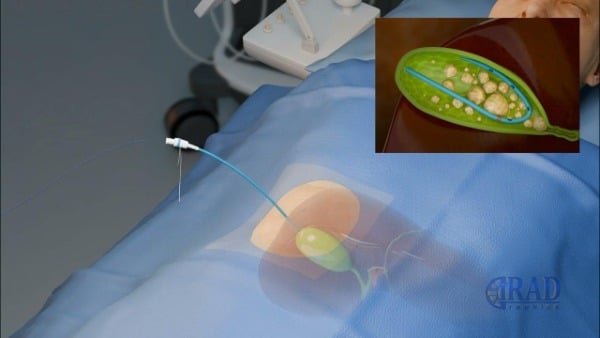

3. Διαδερμική (percutaneous) χολοκυστοστομία

Πώς γίνεται

Η διαδερμική χολοκυστοστομία είναι σήμερα η πιο διαδεδομένη και «κλασική» μορφή χολοκυστοστομίας:

- Εκτελείται από επεμβατικό ακτινολόγο ή χειρουργό.

- Χρησιμοποιείται τοπική αναισθησία και ήπια μέθη, όχι γενική αναισθησία.

- Υπό υπερηχογραφική ή/και αξονική καθοδήγηση:

- Διαπερνάται το δέρμα και, συνήθως μέσω του ηπατικού παρεγχύματος, εισερχόμαστε στη χοληδόχο κύστη.

- Αναρροφάται χολή/πύον και αποστέλλεται για καλλιέργεια.

- Περνά οδηγός σύρμα και πάνω σε αυτό τοποθετείται λεπτός καθετήρας (pigtail) που καθηλώνεται στο δέρμα και συνδέεται με σακουλάκι συλλογής.